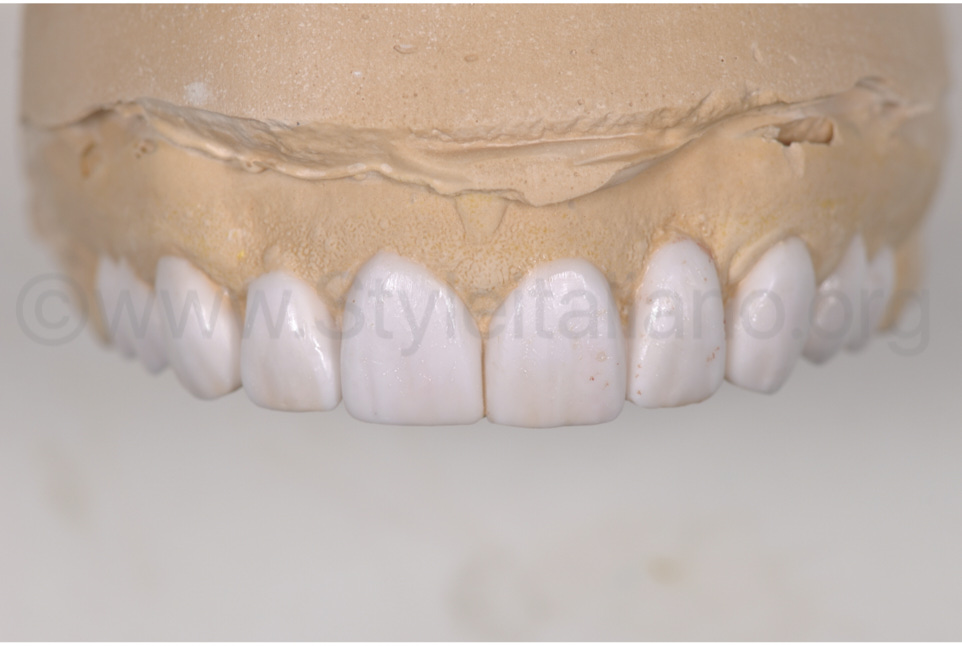

Фото 4.

Зроблено wax-up відновленого зубного ряду з новим дизайном пришийкових зон.

Фото 5.

Видалено старі реставрації, та виконано повторне препарування зубів і контурування ясен.